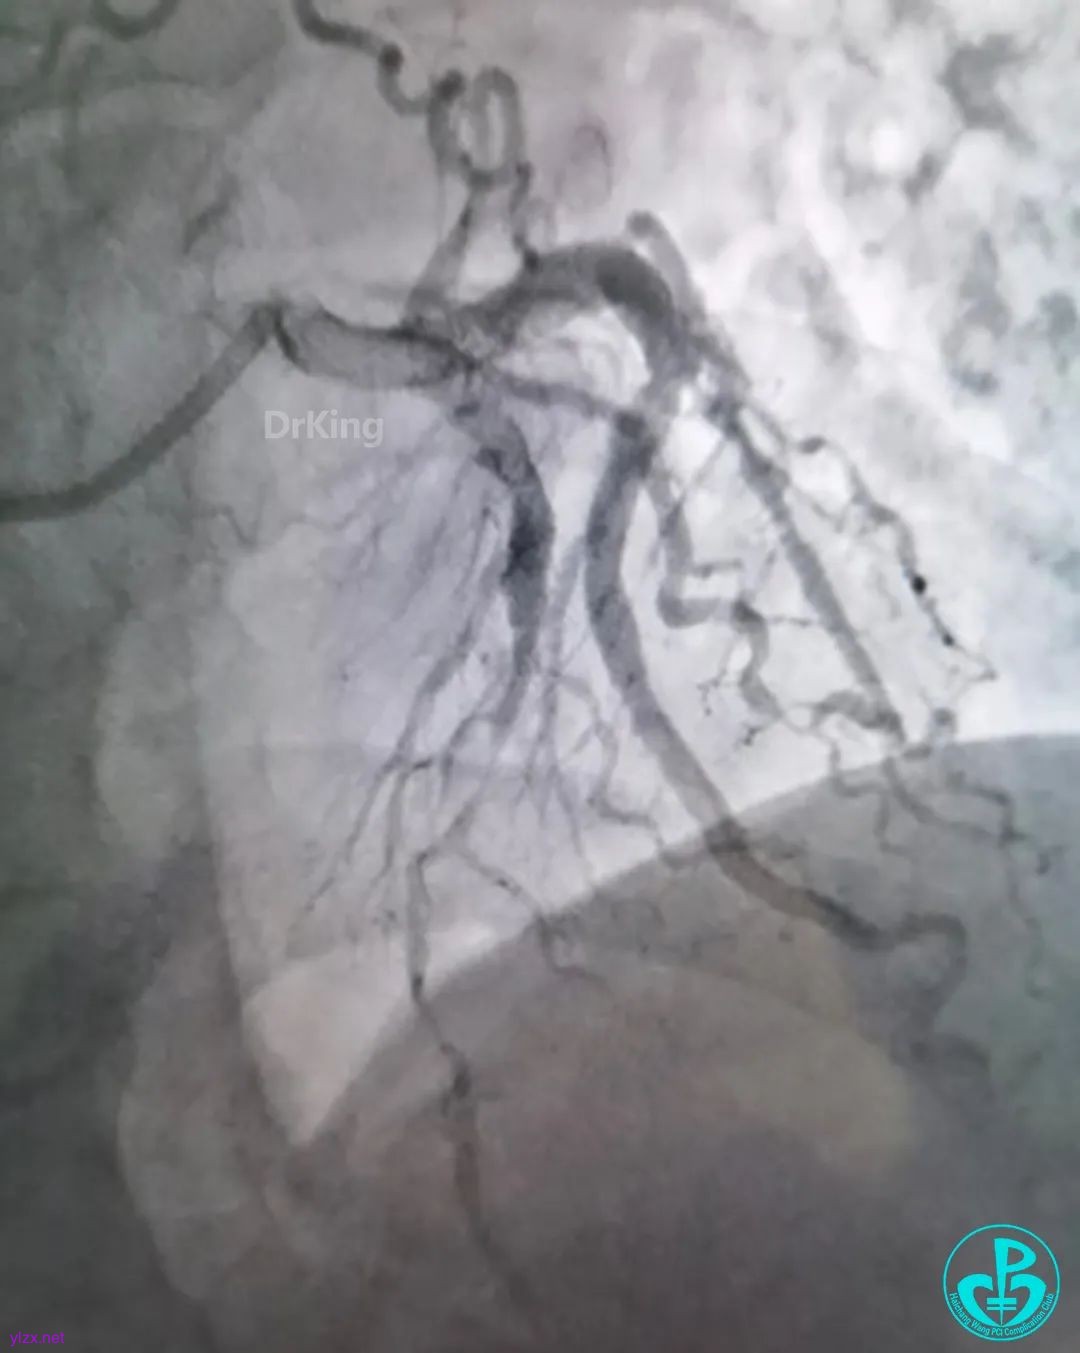

走左边,终于到位,造影。

左边EBU。

简单处理。

血运重建完成,胸痛缓解。生命体征平稳!

股A造影正常,撤台,安返CCU。